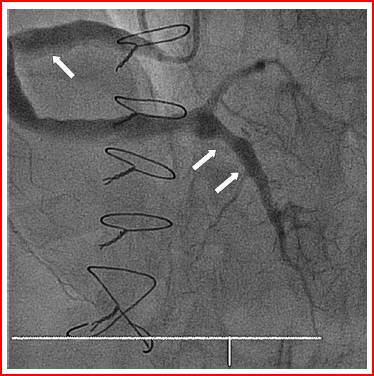

Un paciente varón de 57 años de edad, con antecedentes de disección aórtica tipo A intervenida en el año 2007 y dilatación residual de la aorta descendente de hasta 60 mm es ingresado por un síndrome coronario agudo sin elevación de ST: el paciente refiere sufrir un dolor epigástrico opresivo irradiado al borde cubital de ambos brazos asociado a sudoración profusa. Dura unas tres horas y cuando acude al Servicio de Urgencias está ya asintomático. La tensión arterial es de 160/80 mmHg, el electrocardiograma no muestra alteraciones significativas y presenta una discreta elevación de marcadores de daño miocárdico (creatininfosfoquinasa 233 U/L y troponina I 3.15 ng/mL). Se descarta mediante la tomografía axial computarizada que el cuadro esté relacionado con la progresión de su enfermedad aórtica, comprobándose además que los diámetros aórticos permanecen estables. Queda ingresado en la Unidad Coronaria iniciándose tratamiento convencional del síndrome coronario agudo. Se realiza coronariografía que muestra una marcada ectasia de las arterias coronarias, con varios defectos de llenado a distintos niveles de la coronaria derecha de significado incierto (Fig. 1, flechas; Anexo, vídeo 1 (disponible en la web). Se intenta realizar tromboaspiración, sin que esta sea exitosa. Si bien lo más probable es que sean lesiones trombóticas no se puede descartar que se trate de artefactos motivados por lo llamativamente lento del flujo coronario. Comentado el caso en sesión clínica con los cardiólogos intervencionistas y habiéndose revisado la literatura disponible al respecto se decide, de forma empírica, mantener tratamiento antiagregante y anticoagulante en rango terapéutico durante dos meses y repetir la coronariografía para reevaluar las imágenes dependientes de la coronaria derecha. Este segundo estudio muestra la completa resolución de las lesiones, confirmando el origen trombótico de las mismas (Fig. 2, Anexo, vídeo 2 (disponible en la web). Se discute nuevamente el manejo terapéutico del paciente, valorando las ventajas y los inconvenientes de los distintos regímenes farmacológicos. Conjuntamente y habiéndoselo expuesto al paciente se decide que es razonable, a la vista de la estabilidad de los diámetros aórticos y de la resolución de las lesiones intracoronarias, mantener la anticoagulación de forma crónica suspendiendo la antiagregación. Al cabo de dos años y seis meses el paciente se mantiene asintomático y estable.

Figura 1 Primera coronariografía. Arteria coronaria derecha severamente dilatada. Apréciense defectos de perfusión (flechas) a varios niveles.